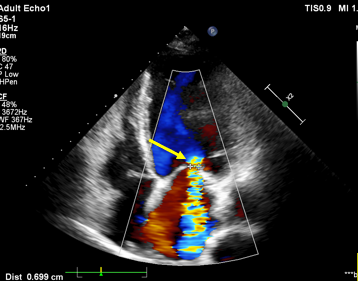

4、判断题:

图中所示的五彩血流信号是指二尖瓣狭窄吗? ( )

选项:

A:对

B:错

答案: 【错】